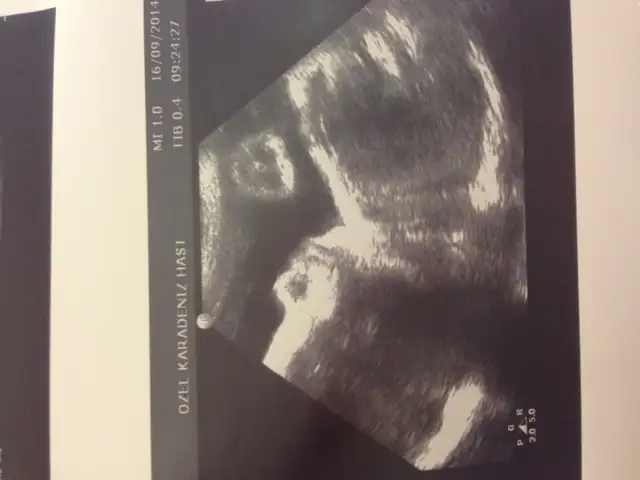

kuzu profilden poz vermişşş